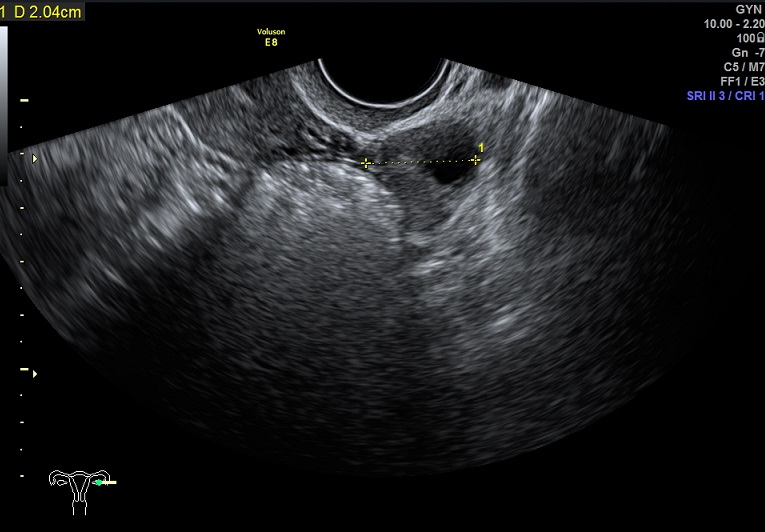

左卵巢: 大小3.5x2.0x1.7cm 体积:6.2 窦卵泡:无 左卵巢见两枚大卵泡:1.9x1.2x1.0cm、1.5x1.2x1.1cm 卵巢间质血流:9.8cm/s RI:0.49